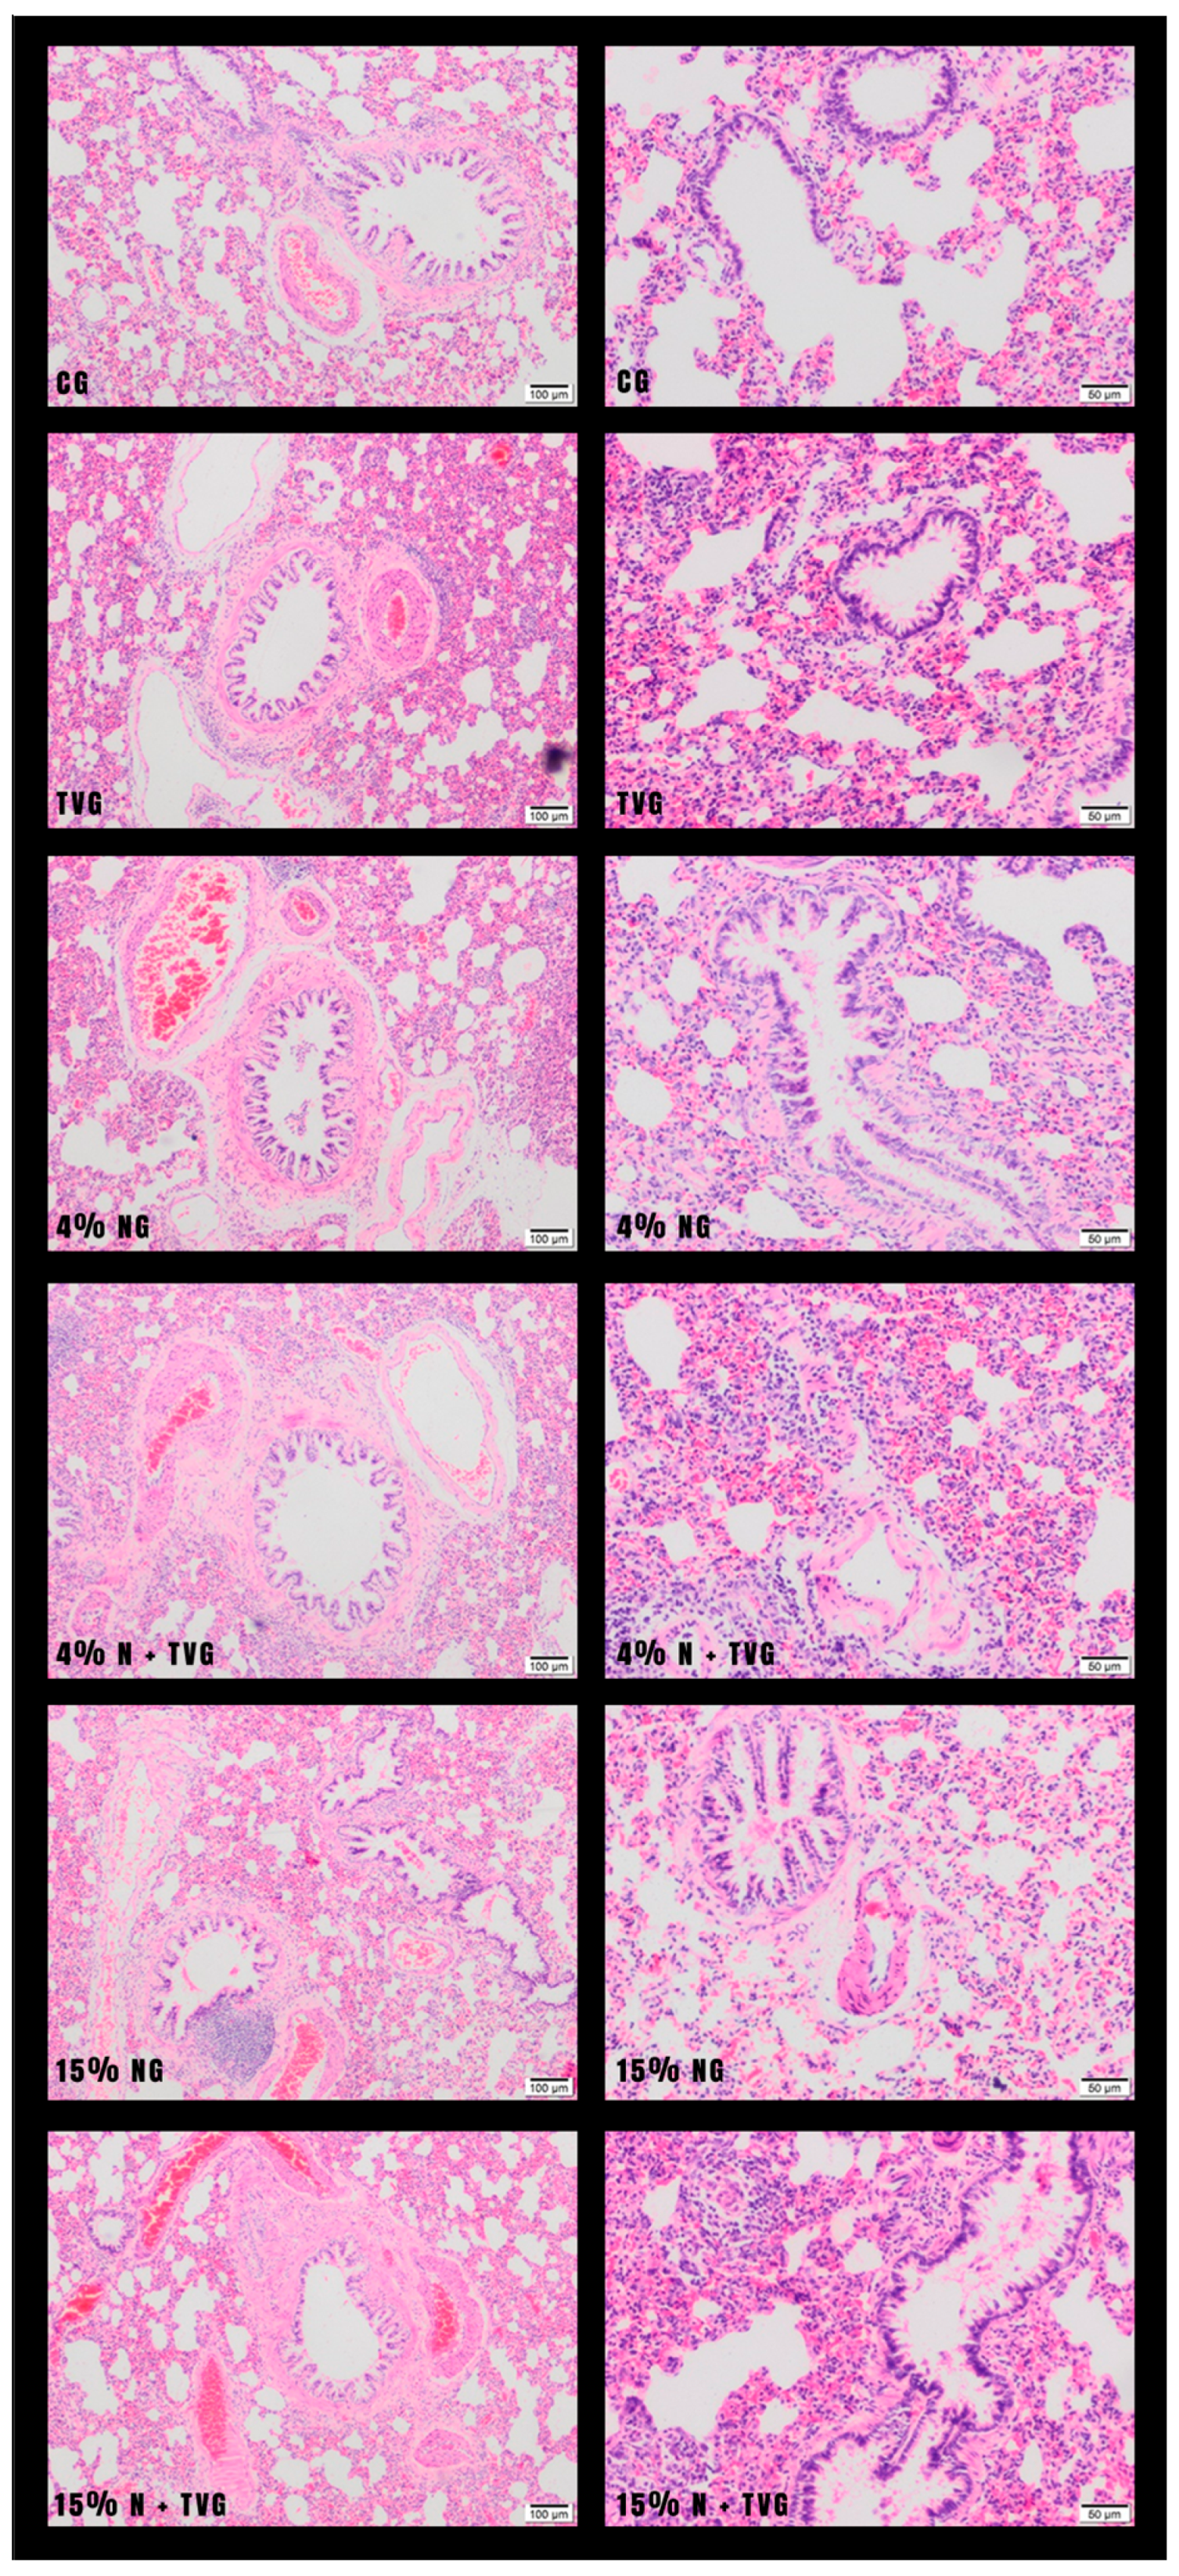

In hematoxylin–eosin (HE) examinations of lung tissue sections, normal lung tissue histology was observed in CG and TVG. While mild fibrosis and inflammation were observed in the lung tissue in 4% NG, significant inflammation and fibrosis were observed in 15% NG. In 4% N + TVG, no significant change was observed in alveolar enlargement and fibrous band formation due to the lesser damage in 4% NG. A significant improvement was observed in 15% N + TVG regarding alveolar enlargement and fibrous band formation compared with 15% NG (Figure 1).

In control and T. vulgaris group samples, mostly normal connective tissue formation was observed around the bronchioles. Mild fibrosis was observed in the 4% NaOCl group, and intense fibrosis in the 15% NaOCl group. In addition, inflammatory cells in the alveolar lumens of the lung tissue and inflammatory thickening in the interalveolar septum were detected in the 15% NaOCl group. These findings were not evident in the 4% NaOCl group. It was observed that intense fibrosis, inflammation, and other deterioration in the 15% NaOCl group were significantly reduced with T. vulgaris application.

In the lung tissue, 15% NG showed localized degeneration of the squamous and cubic cells lining the alveoli, epithelial eruptions in the alveolar spaces, and irregular enlargement due to the merging of the alveolar spaces. In addition, inflammatory thickening and destruction of the interalveolar septum, inflammatory cells in the alveolar lumens, diffuse macrophages, and neutrophils were observed. Intense fibrosis in the lung, significant edema in the bronchiolar epithelium, and the perivascular areas of the vessels accompanying the bronchioles were observed (Figure 2). Although similar histopathological findings were seen in 4% NG, they were not as significant as in 15% NG.